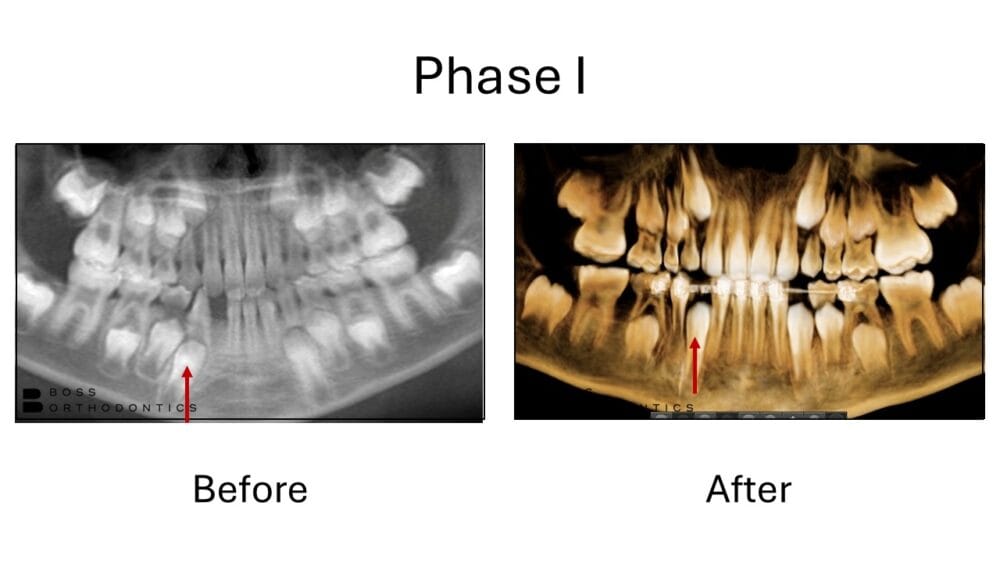

Look at these amazing smile transformations! Before and after orthodontic treatment photos. Braces before and after, clear aligner before and after, phase I before and after, and more. Click photos to enlarge.Â

At Boss Orthodontics, we take immense pride in our patientâs care and work diligently to achieve stunning orthodontic before and after transformations, showcasing the profound impact that orthodontic treatment has on our patients' smiles. Our before and after smile gallery highlights the remarkable changes achieved through braces and clear aligners/ Invisalign before and after treatment. Â Each transformation underscores our commitment to delivering personalized care and exceptional results, reflecting our dedication to enhancing both aesthetics and oral health.